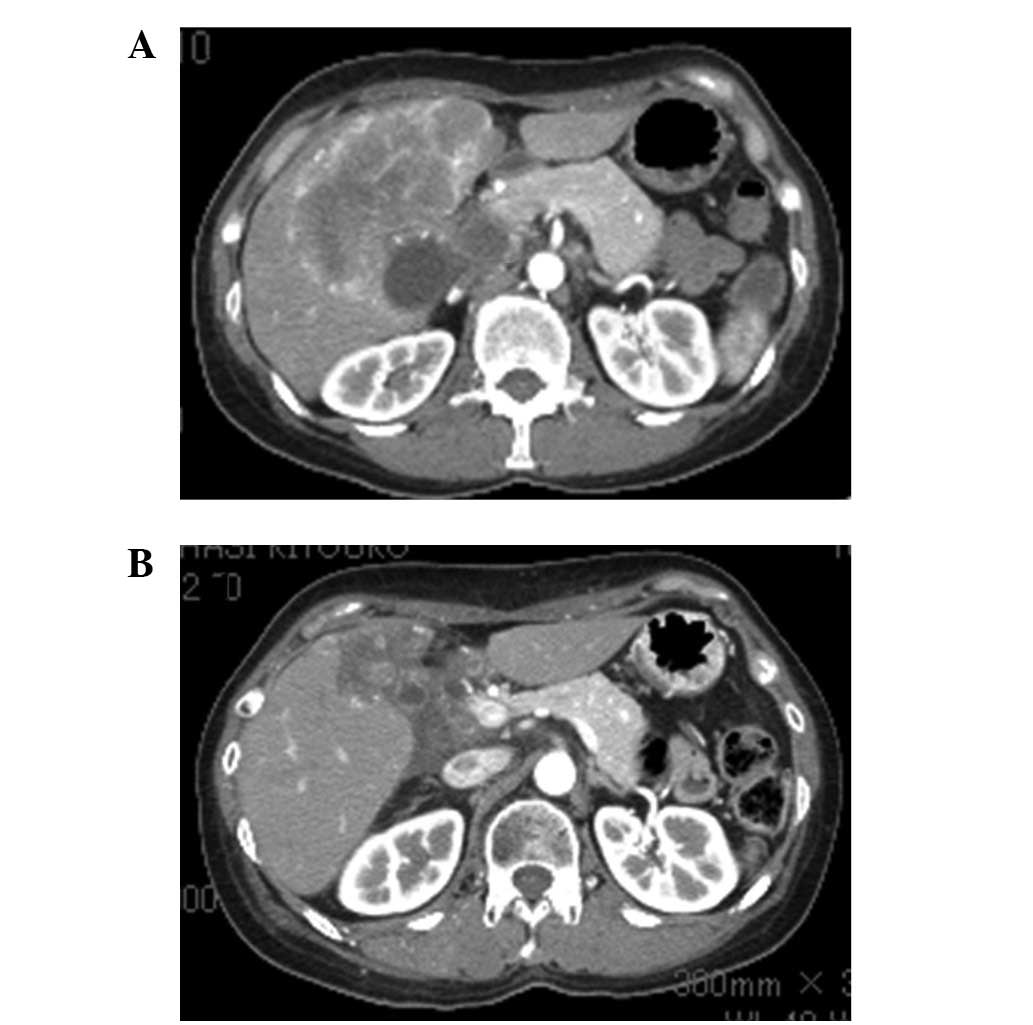

Figure 1.

Abdominal CT (A) before and (B) after treatment. (A) Abdominal CT showing a large gallbladder tumor infiltrating the liver and liver metastasis. (B) The tumor size was reduced following chemotherapy with low-dose paclitaxel.

Figure 2.

Drip-infusion cholangiography (DIC)-CT (A) before and (B) after treatment. (A) DIC-CT showing stenosis of the hilar bile duct. (B) Stenosis of the hilar bile duct improved following the administration of low-dose paclitaxel and radiation.

A 56-year-old woman in good health was admitted to our hospital with right upper quadrant pain. Physical examination was notable for right upper quadrant tenderness and hepatomegaly. CT of the abdomen revealed multiple hepatic nodules, a thick gallbladder wall and dilation of the intrahepatic bile duct (Fig. 1A). CEA was 14.3 IU/ml (upper limit of normal, 5.0 IU/ml) and CA19-9 was 58 IU/ml (upper limit of normal, 37 IU/ml). The patient was diagnosed with unresectable gallbladder cancer with multiple liver metastasis and local infiltration to the liver and hilar bile duct (Fig. 2A).

The patient was treated with oral S-1 (60 mg/m2) twice daily for 14 days plus gemcitabine (800 mg/m2) administered on days 8 and 14 [every 21 days as previously described for pancreatic carcinoma (8)]. After 4 cycles of therapy, the doses were reduced as the patient developed neutropenia. After 9 cycles of therapy, CT showed evidence of stable disease; however, the serum CEA level was increased (Fig. 3). Therefore, the chemotherapy regimen was changed to weekly paclitaxel (60 mg/m2). After 12 cycles of therapy, paclitaxel was reduced to 30 mg/m2 due to neutropenia. The patient completed 32 cycles of paclitaxel therapy and CT showed evidence of a partial response (Fig. 1B) and stenosis of the hilar bile duct was improved (Fig. 2B). At the beginning of paclitaxel therapy, irradiation of the stenotic hilar bile duct was performed. The toxicities evaluated were leucopenia (grade 2), general malaise (grade 1) and shedding of hair; however, no serious adverse events were observed. Therefore, the patient was treated at the outpatient clinic, without any impairment in the quality of life (QOL).